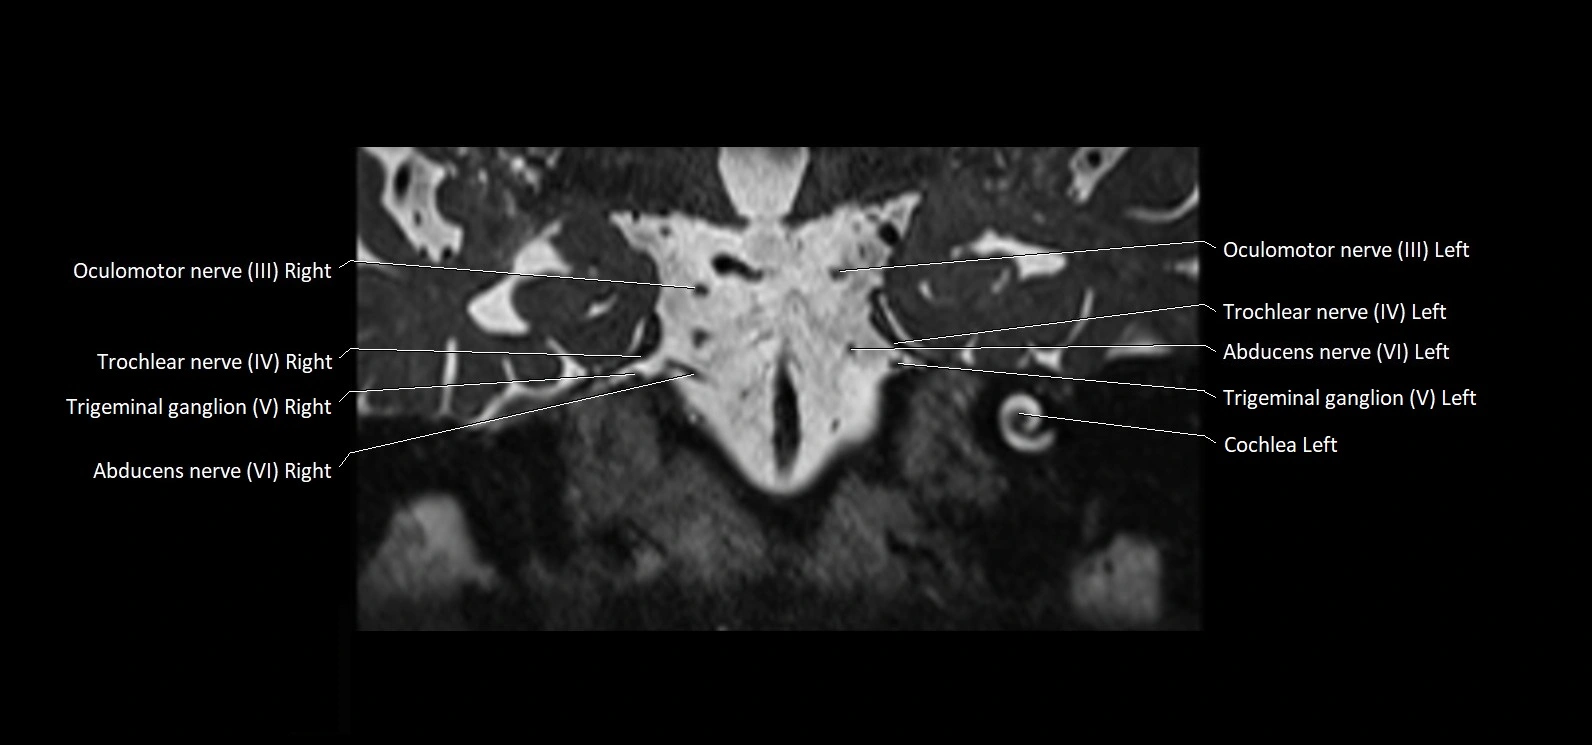

MRI Appearance

• The abducens nerve is a small, thin, linear structure

• Best visualized on high-resolution T2-weighted 3D MRI sequences (e.g., FIESTA or CISS)

• Seen as a hypointense (dark) line running from the brainstem at the pontomedullary junction, traversing the prepontine cistern, and entering Dorello’s canal under the petrosphenoidal ligament, then into the cavernous sinus, and finally the orbit

• May be challenging to visualize in standard MRI due to its small size

• Pathology may be inferred by absence, displacement, or enhancement of the nerve

MRI images

image